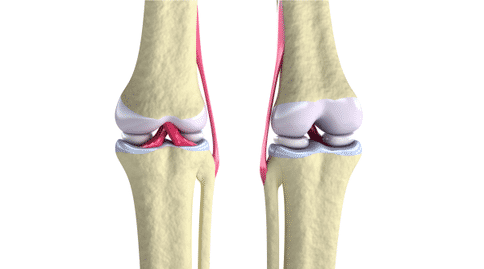

幼年特發(fā)性關(guān)節(jié)炎是兒童中常見的風濕病,但它表現(xiàn)為多種不同的形式,嚴重程度較高,且預(yù)后較差。這種疾病的多樣性不利于醫(yī)生對患者的治療,尤其是在疾病早期,醫(yī)生很難辨別疾病的類型,效果較差。

多關(guān)節(jié)炎型:女孩多見,起病年齡有2個高峰,1~3歲和青春早期。受累關(guān)節(jié)≥5個,尤以指趾小關(guān)節(jié)受累比較突出。起病緩慢或急驟,表現(xiàn)為關(guān)節(jié)僵硬、腫痛和局部發(fā)熱,一般很少發(fā)紅。

通常從大關(guān)節(jié)開始,如膝、踝、肘,逐漸累及小關(guān)節(jié),出現(xiàn)梭狀指。約1/2病兒頸椎關(guān)節(jié)受累,致頸部活動受限。顳頜關(guān)節(jié)受累造成咀嚼困難。少數(shù)發(fā)生環(huán)、杓(喉部軟骨)關(guān)節(jié)炎,致聲啞及喉喘鳴。晚期可出現(xiàn)髖關(guān)節(jié)受累及股骨頭破壞,發(fā)生運動障礙。關(guān)節(jié)癥狀反復(fù)發(fā)作、持續(xù)數(shù)年者關(guān)節(jié)僵直變形,關(guān)節(jié)附近肌肉萎縮。

少關(guān)節(jié)炎型:通常在1~3歲起病,受累關(guān)節(jié)不超過四個。膝關(guān)節(jié)經(jīng)常受累,其次是踝關(guān)節(jié),再次是手的小關(guān)節(jié),但幾乎任何關(guān)節(jié)均可受累。約20%的少關(guān)節(jié)型JIA患兒發(fā)生虹膜睫狀體炎,抗核抗體陽性患兒更易發(fā)生。